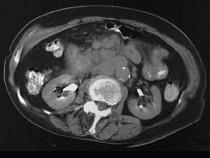

问题 女,28岁,腹痛,恶心呕吐,大便潜血阳性,轻度腹胀,中腹部可扪及一不规则肿块,影像表现如图,最可能的诊断是()

选项 A.小肠腺癌 B.小肠非霍奇金淋巴瘤 C.小肠Crohn病 D.小肠结核 E.腹膜后淋巴结结核

答案 B